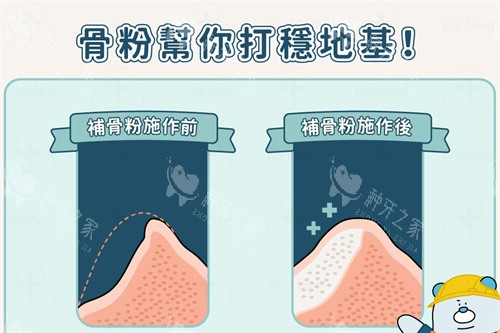

奥齿泰种植系统提供了多种型号的种植体,如TSIII超短种植体、TSIV种植体等,以满足不同患者的种植需求。这些种植体适用于各种复杂的口腔情况,如牙槽骨吸收、疏松骨质等。多样化的产品系列不仅为患者提供了更多的选择,也提高了种植的成功概率和稳定性。